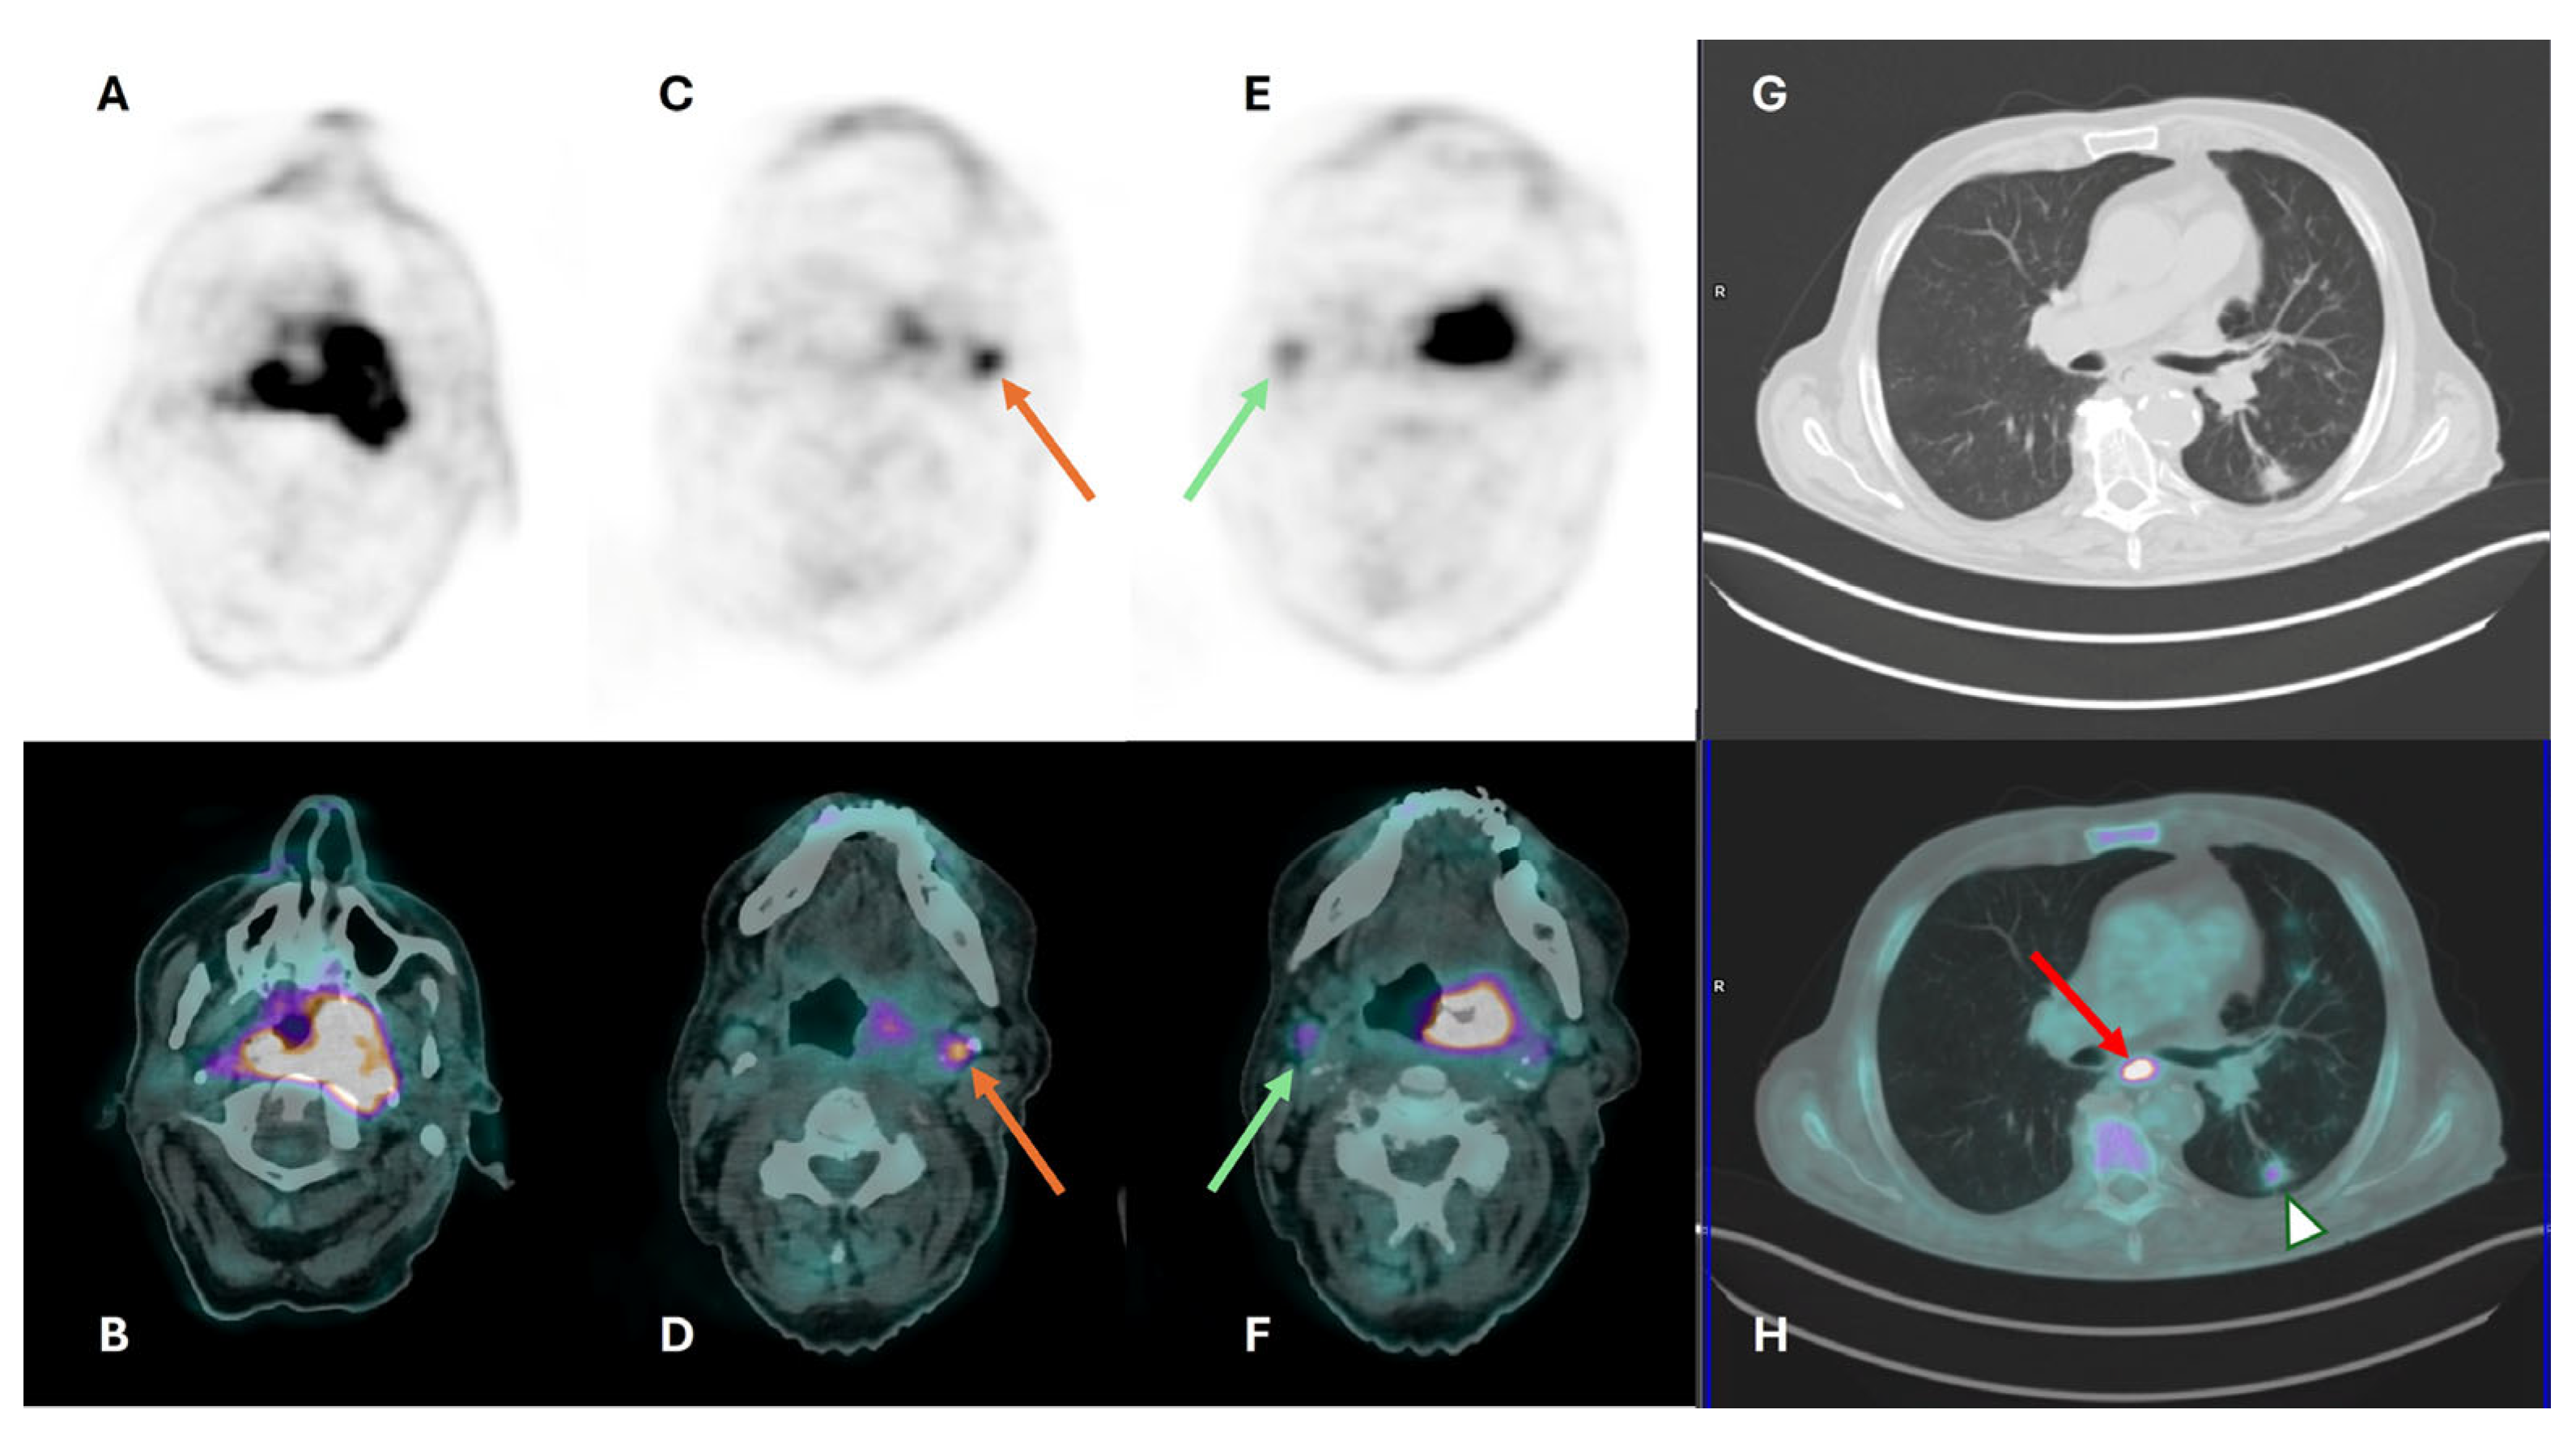

- Castaldi, P.; Rufini, V.; Bussu, F.; Miccichè, F.; Dinapoli, N.; Autorino, R.; Lago, M.; De Corso, E.; Almadori, G.; Galli, J.; et al. Can “early” and “late” 18F-FDG PET-CT be used as prognostic factors for the clinical outcome of patients with locally advanced head and neck cancer treated with radio-chemotherapy? Radiother. Oncol. 2012, 103, 63–68. [Google Scholar] [CrossRef] [PubMed]